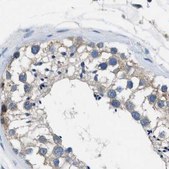

Anti-PGR antibody produced in rabbit

immunohistochemistry: 1:20- 1:50

The Human Protein Atlas project can be subdivided into three efforts: Human Tissue Atlas, Cancer Atlas, and Human Cell Atlas. The antibodies that have been generated in support of the Tissue and Cancer Atlas projects have been tested by immunohistochemistry against hundreds of normal and disease tissues and through the recent efforts of the Human Cell Atlas project, many have been characterized by immunofluorescence to map the human proteome not only at the tissue level but now at the subcellular level. These images and the collection of this vast data set can be viewed on the Human Protein Atlas (HPA) site by clicking on the Image Gallery link. We also provide Prestige Antibodies® protocols and other useful information.

- IHC tissue array of 44 normal human tissues and 20 of the most common cancer type tissues.